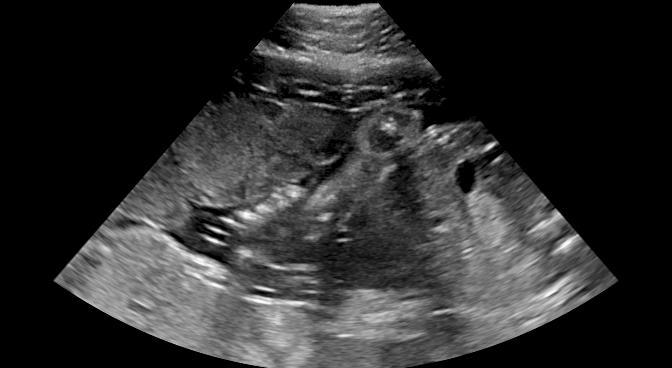

Fig. 9 qualitatively shows that shadow confidence maps are able to improve the performance of US image fusion algorithms with different weighting strategies. Fig. 9 also shows the difference between adding two different types of confidence maps. These two types of confidence maps are generated by the confidence estimation network which are separately trained by either MSE or Sigmoid loss. Fig. 9 (a) to (d) illustrate image fusion results for the same case using different combinations of weighting strategies and loss functions. The difference maps indicate that shadow confidence maps are capable of improving image fusion performance. Fig. 9 (e) to (h) show image fusion results on four different cases. We randomly select two positively affected cases (Fig. 9 (e) and (f)) to show visual improvement. We additionally show two randomly selected examples (Fig. 9 (g) and (h)) that don’t show perceptually significant improvements after adding shadow confidence maps. Quantitative evaluation for image fusion is not possible because of lacking a ground truth for US compounding tasks.

-G Examples for Image Fusion

Fig.15 shows more examples of the multi-view image fusion task which include the original multi-view images. From the column (a-b) of Fig.15, we can see that the original images contain strong shadow artifacts that can affect the anatomical analysis. The image fusion task aims to use complementary information from images with different views for reducing artifacts and increasing anatomical information. Column (e-f) enlarge the areas within the bounding boxes in column (c-d). Column (g) shows the difference masks between column (e)and (f). The difference masks clearly indicates the improved performance of image fusion after adding shadow confidence maps for Gaussian weighting strategy as well as Intensity and Gaussian weighting strategy.